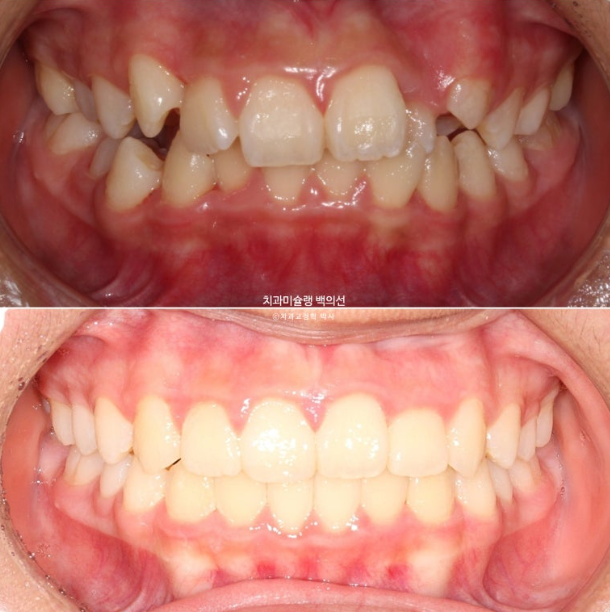

24.02~25.07

이제 전 후 비교해 보겠습니다.

총 치료기간은 1년 6개월이고 중간에 중심선 이슈로 잠시 쉬는 시간이 4개월 있었습니다.

재제작은 총 2회 했습니다.

치료결과가 어린이 교정이 아닌 정식 성인교정 치료 결과에 준한만큼 유지장치도 철저히 들어갑니다.

어긋난 중심선이 맞아졌으며 기울어진 앞니 치축도 좋아졌습니다.

앞니가 깊게 물리는 과개교합도 좋아졌습니다.